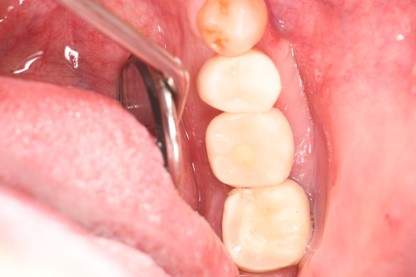

症例写真-2

- Befor

- 途中経過

- After

| 年齢 | 50代・男性 |

|---|---|

| 主訴 | 右下歯が疼く |

| 治療内容 | ・右下6番インプラント ※1:FGG(遊離歯肉移植術)とは、足りない歯ぐきを上顎から上皮を切り取り移植する外科手術 |

| 治療費 | 合計:902,000円(税込) ■内訳 |

| 治療期間 | 9ヵ月 |

| 治療方針 | 右下の当該歯は歯根破折により保存不可能と診断しました。歯周疾患も伴っていたため抜歯後に骨吸収※1が大きく起こることが予測できました。チタンメッシュ併用骨再生誘導法(GBR※2)を選択しインプラント埋入と同時に行い自然な歯槽骨のラインを再現しました。またGBRを行う際にインプラント辺縁の付着歯肉の減少が起こる為、遊離歯肉移植術(FGG※3)を行い清掃性を考慮した形態に仕上げました。 ■治療方針の解説 治療した右下の歯をレントゲンで撮影したところ根本の部分に黒く写る箇所があり「根尖性慢性周囲炎※1」と診断。また歯周病も進行していました。 ※1 骨吸収・・・歯槽骨という歯を支える骨がなくなっていくこと |

| 担当者所見 | 主訴の右下だけでなく歯茎の腫れ、発赤があり不良補綴や不良充填など他にも治療箇所が多数ありました。プラークコントロールが不良であった為まずはブラッシング指導を行いセルフケアの重要性を理解していただくところからスタートしました。 右下6番の歯はインプラント治療を行なった結果審美的にも機能的にも患者様の満足を得ることができました。骨造成と歯肉移植も行なった為インプラントを支える十分な歯周組織の獲得ができたと思っております。 |